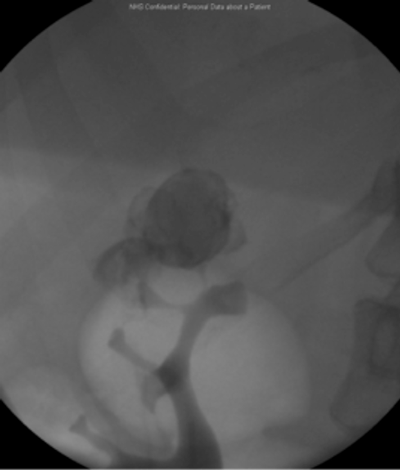

The upper pole was incised, the stone delivered and the calyx closed with 3-O PDS. A retrograde examination at three months revealed no leak.

Pre-laparoscopy retrograde examination.